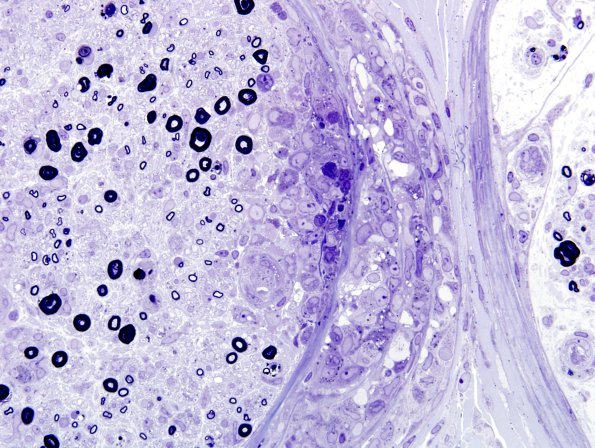

3B5C Sarcoid (Case 3) Plastic 18

Multiple magnifications of granulomatous perineurial infiltrates. (Plastic sections